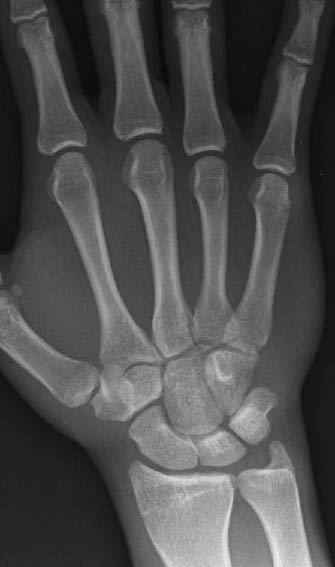

Figure 2: Normal Wrist PA Radiograph

Plain radiographic imaging should be the initial diagnostic study in patients with wrist injuries. The views obtained may include postero-anterior (see Figure 2) and lateral views, along with radial and ulnar oblique views. A scaphoid view is often obtained in cases with clinical suspicion for scaphoid fracture, which is a postero-anterior view with the wrist in ulnar deviation. (See Figure 3.) Despite multiple plain radiographic images, up to 14% of scaphoid fractures are not detected on radiographs taken soon after the injury.1,4,5 Retrospective studies suggest that 10-33% of patients with a proven fractured scaphoid had negative initial radiographs.9